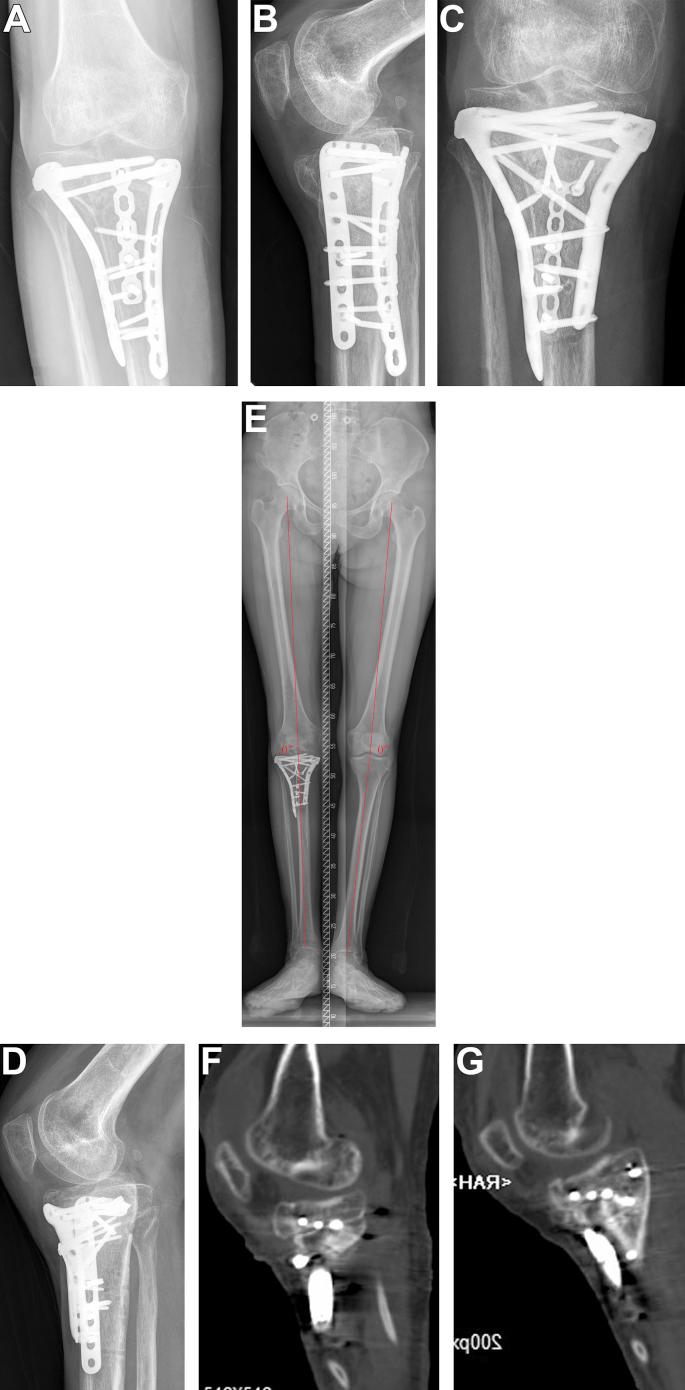

The aim of this study was to evaluate our treatment algorithm and results in revision surgery of malunited tibial plateau fracture after failure of initial treatment.

Our revision strategy was as follows: First, we determined the presence of any infection. Second, we determined whether the patient required total knee arthroplasty (TKA). Third, based on the characteristics of the tibial plateau fracture malunion, patients underwent one of the following surgical methods to achieve reduction: original fracture line osteotomy, tibial tubercle + original fracture line osteotomy, fibula head + original fracture line osteotomy, and metaphyseal open window reduction rod technique. The results was assessed with healing time, Rasmussen score, knee range of motion and complication rates.

A total of 25 patients 16 men and 9 women; Mean age: 47.4 years (range: 35-63 years) underwent tibial plateau fracture revision operation. The time interval between the two surgeries was 2-24 months. The follow-up time was 12-30 months, and the operation time was 120-300 min. All patients received bone union at the last follow-up. The healing time was 3-6 months. The postoperative Rasmussen score was 19-29 (mean 23.8) compared with 14.4 points before the operation (p < 0.05). The postoperative knee joint activity was 60-110° (mean 95.0°), compared with 57.8° before the operation (p < 0.05). Six patients still had a 2-mm collapse on the articular surface, and 4 patients still had slight valgus (<5°). Except for 2 TKA cases, fracture reduction was excellent in 15 cases and good in 8 cases, with a good rate of 100%. Superficial wound infections occurred in 3 patients.

Because revision of tibial plateau fracture malunion caused by failure of initial treatment is difficult, it is necessary to create a detailed surgical plan before the operation. Satisfactory clinical effects can be obtained if the correct revision strategy is used. The key to success is adopting a proper revision strategy according to the unique characteristics of the patient's tibial plateau fracture malunion.